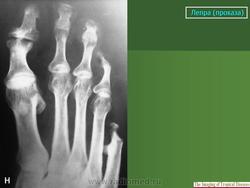

В третьей группе костных изменений при проказе (рис. 217, 218) сочетаются элементы первых двух групп, т. е. специфические и неспецифические. Из особенностей проказы вытекает крайняя неповторяемость частных проявлений в каждом индивидуальном случае заболевания.